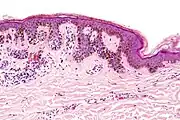

| Dysplastic nevus | Usually a compound nevus with cellular and architectural dysplasia. Like typical moles, dysplastic nevi can be flat or raised. While they vary in size, dysplastic nevi are typically larger than normal moles and tend to have irregular borders and irregular coloration. Hence, they resemble melanoma, appear worrisome, and are often removed to clarify the diagnosis. Dysplastic nevi are markers of risk when they are numerous, such as in people with dysplastic nevus syndrome. According to the National Institute of Health (NIH), doctors believe that, when part of a series or syndrome of multiple moles, dysplastic nevi are more likely than ordinary moles to develop into the most virulent type of skin cancer called melanoma.[22] | ![]() In this case, the central portion is a complex papule, and the periphery is macular, irregular, indistinct and slightly pink. |

Characteristic rete ridge bridging, shouldering, and lamellar fibrosis. H&E stain.